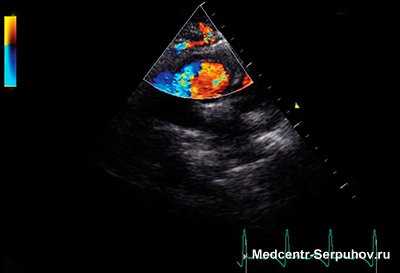

Основным методом выявления С. ш. является Аускультация. Для анализа амплитудно-частотной характеристики С. ш. и их связи с определенными фазами систолы и диастолы сердца применяют фонокардиографию (Фонокардиография). Для выявления и оценки С. ш. с помощью аускультации рекомендуется выслушивать сердце в положении больного не только лежа на спине, но и, при необходимости, в положении на левом и на правом боку, на животе, в положении сидя и стоя, в фазах глубокого вдоха и выдоха, иногда также до и после физической нагрузки, приема нитроглицерина. Выслушивание проводится в так называемых стандартных точках, т.е. в определенных участках прекардиальной области (рис. 1), соответствующих местам проекции С. ш. от отдельных клапанов: 1) в области верхушки сердца — от двустворчатого (митрального) клапана (хотя сам двустворчатый клапан проецируется выше — у места прикрепления III ребра к грудине); 2) во втором межреберье, у правого края грудины, — от клапана аорты; 3) во втором межреберье, у левого края грудины, — от клапана легочного ствола; 4) у правого края нижней трети грудины — от трехстворчатого клапана; 5) в четвертом межреберье у левого края грудины (пятая точка, или точка Боткина — Эрба) — для выслушивания диастолического шума аортальной недостаточности, а в ряде случаев и шумов, связанных с поражениями митрального клапана. При выявлении С. ш. аускультацию не ограничивают стандартными точками, определяя места наилучшего выслушивания шума, его проведение на сосуды шеи или другие сосуды. При фонокардиографическом исследовании микрофон располагают в стандартных точках аускультации.

- Аускультация - высокоинформативный метод диагностики заболеваний сердечно-сосудистой системы, основанный на выслушивании звуковых явлений, связанных с деятельностью сердечно-сосудистой системы.

- Эхокардиография (ЭКГ).